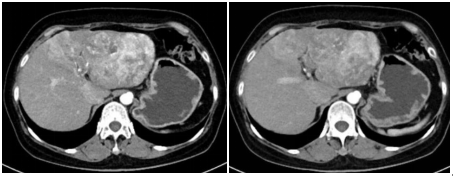

自2020-10-14口服仑伐替尼 8mgQD;2020-10-28行经肝动脉栓塞术(TACE);2020-10-29/11-20/12-11分别行3次免疫治疗(卡瑞利珠单抗 200mg 静脉注射);于2020年12月进行评估,复查AFP 7103 ng/ml,胸部CT提示双肺转移灶明显缩小,腹部增强CT提示肝占位较前局限、缩小。

于2021-1-5对该患者行腹腔镜下左半肝切除,术后1.5月AFP降至正常(2021-2-22 AFP 14 ng/ml),目前无瘤生存13个月。

1-6.png

图示:治疗前后肝脏及肺部病灶对比。